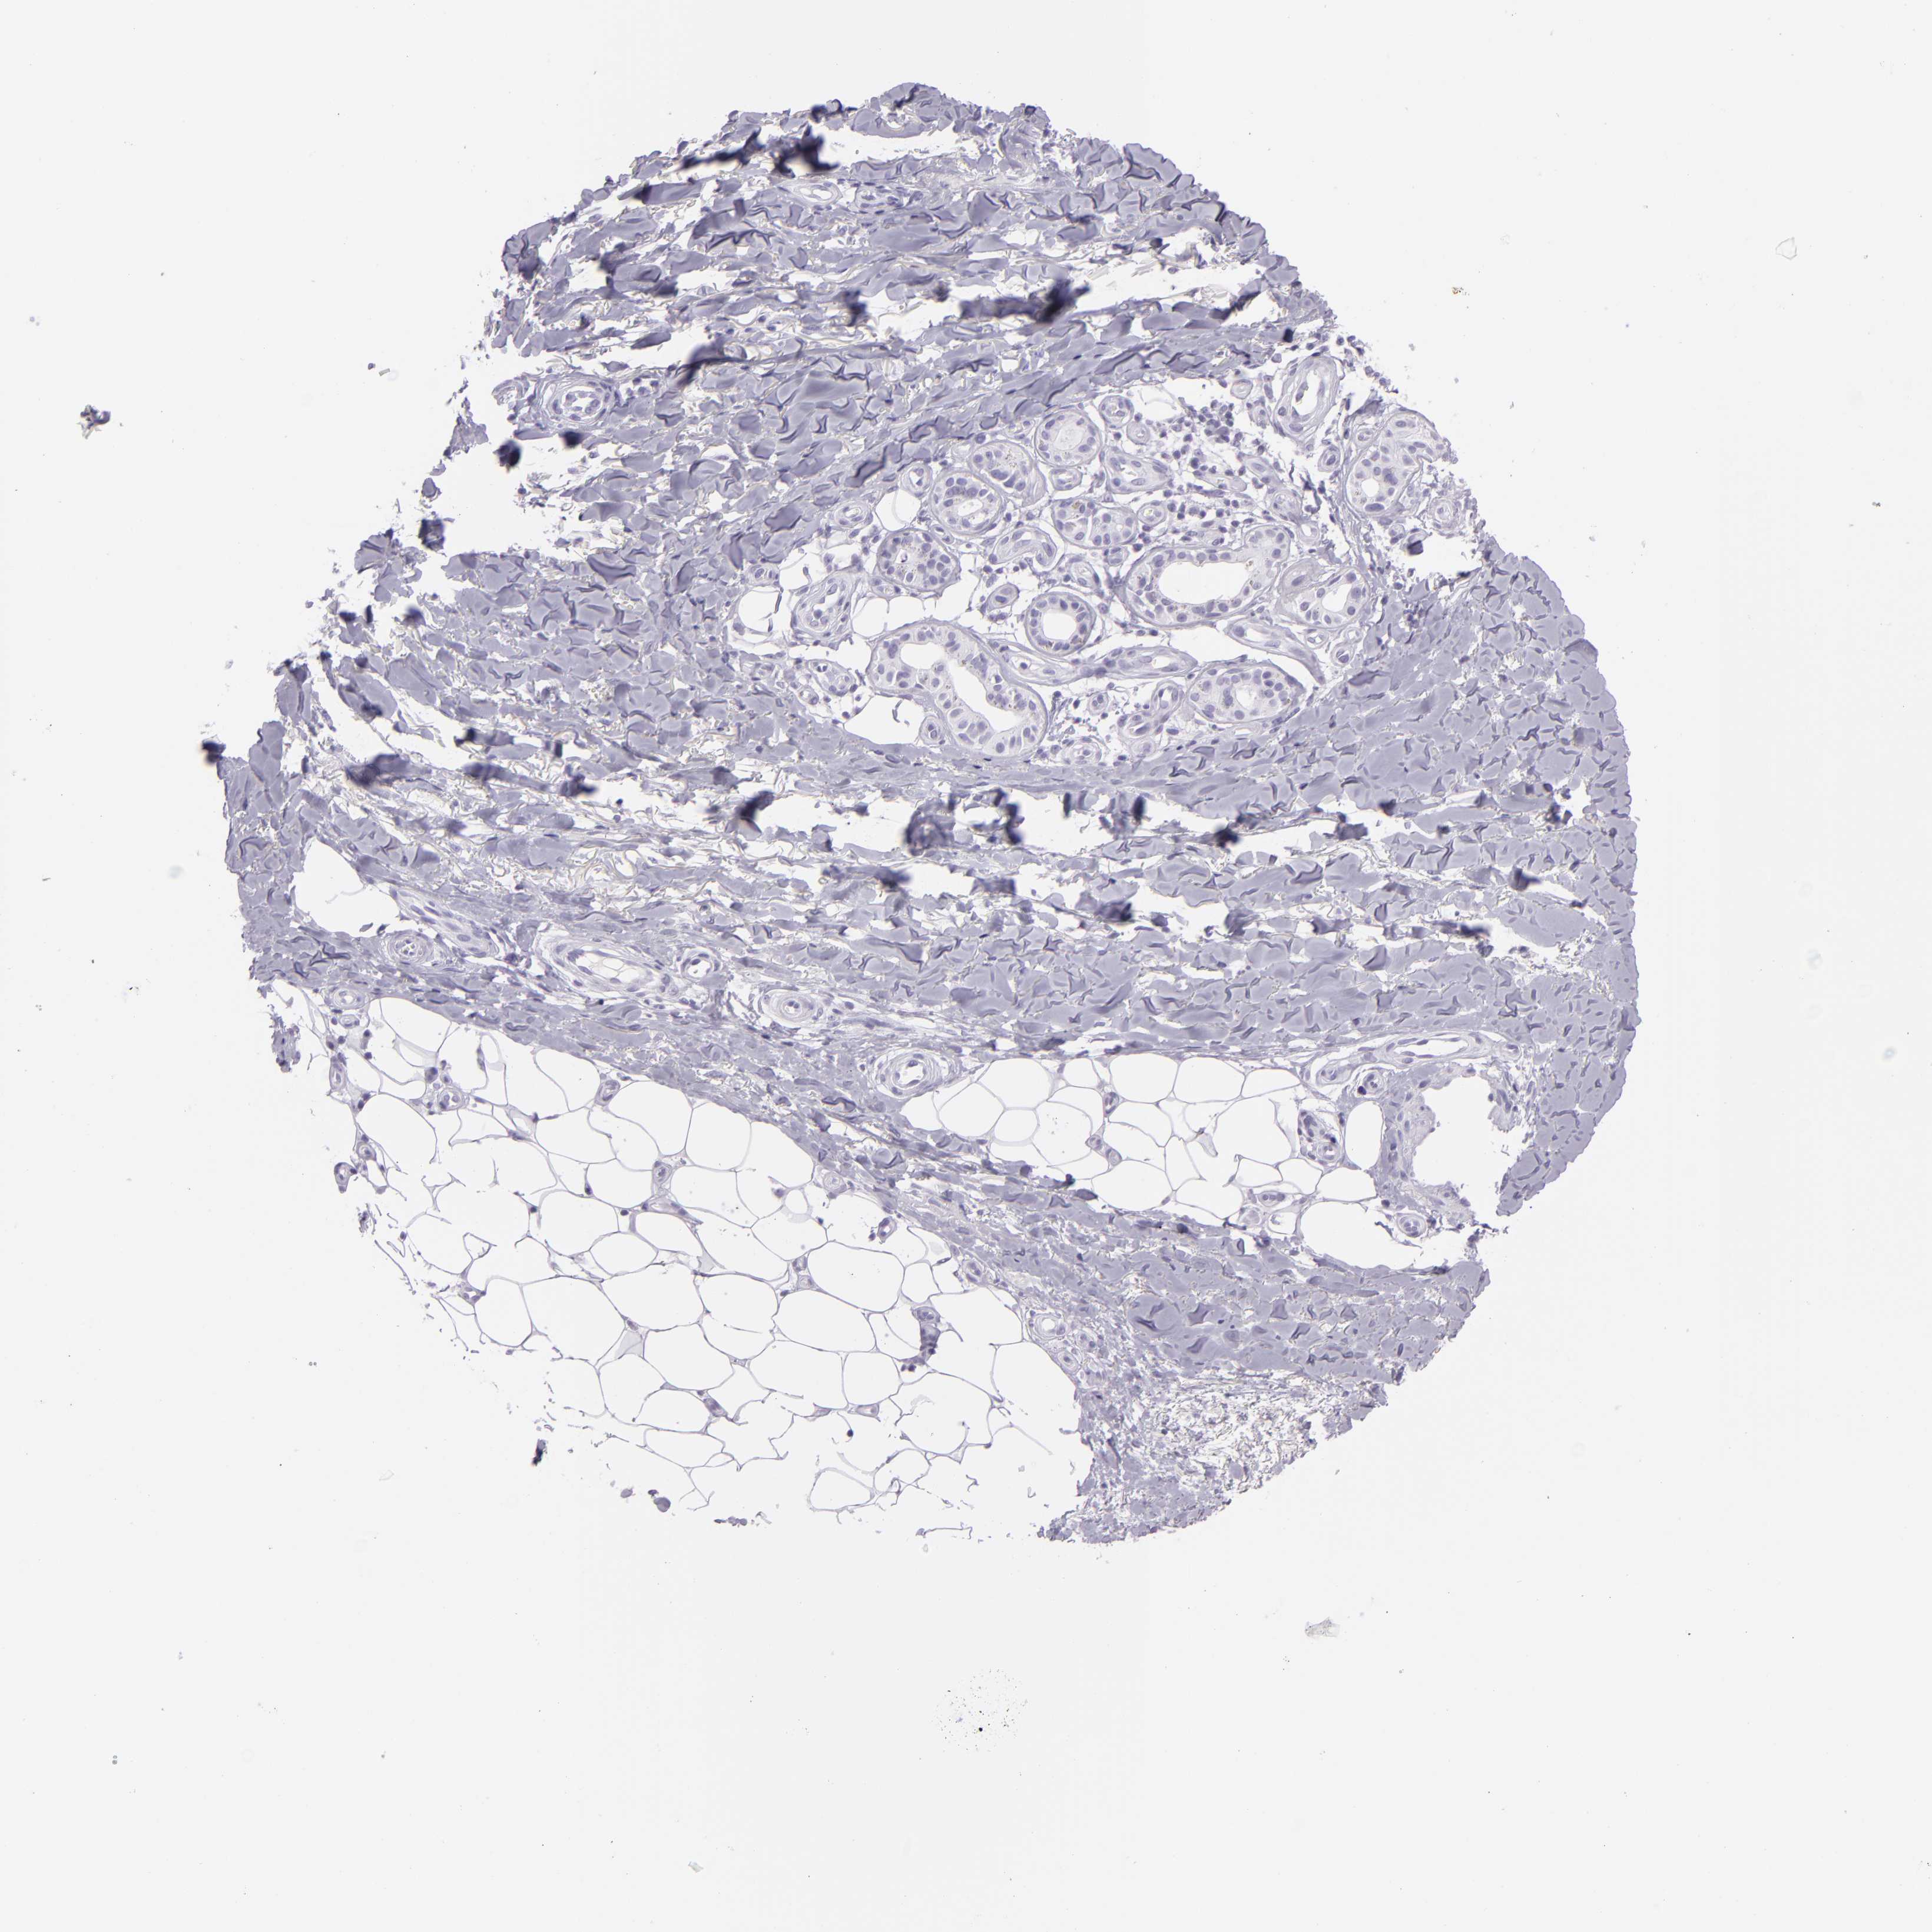

SKIN CANCER - Protein expressioni

A mouse-over function shows sample information and annotation data. Click on an image to view it in a full screen mode. Samples can be filtered based on level of antibody staining by selecting one or several of the following categories: high, medium, low and not detected. The assay and annotation is described here.

Antibody stainingi

Antibody staining in the annotated cell types in the current human tissue is reported as not detected, low, medium, or high, based on conventional immunohistochemistry profiling in selected tissues. This score is based on the combination of the staining intensity and fraction of stained cells.

Each image is clickable and will lead to virtual microscopy that enables deeper exploration of all samples and also displays staining intensity scores, fraction scores and subcellular localization as well as patient and tissue information for each sample.

Antibody CAB002165

Basal cell carcinoma